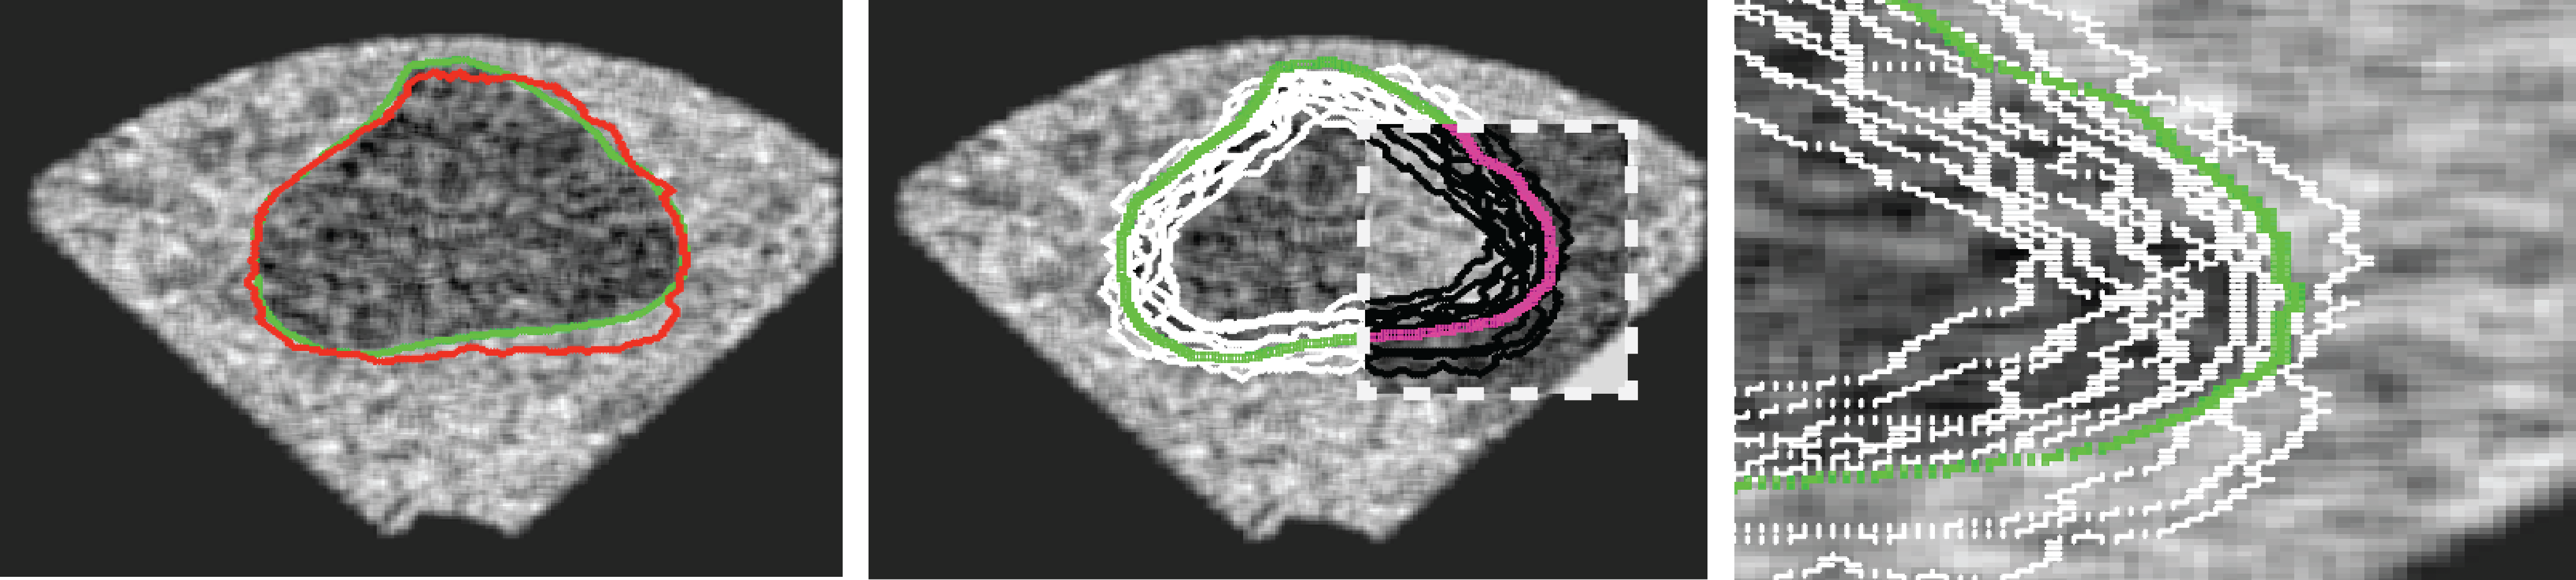

In the previous section, we simulated images in order to exploit “perfect segments”. In this section, we validate our approach using actual MR images of prostates. The image data from 15 patients were manually delineated by 5 oncologists.

The MR images used in this study were derived from an online database444http://prostatemrimagedatabase.com/. The database contains T2-weighted MR volume datasets, provided by Brigham and Women’s Hospital, the National Center for Image-guided Therapy, and Harvard Medical School. The images comprised T2-weighted MR images (T2W-MR) with endorectal coils. The pulse-sequence groups in the DICOM headers of most of the T2-weighted images were marked fast-spin echo (FSE), although some were marked as fast-relaxation fast-spin echo-accelerated (FRFSE-XL). The dataset contained images with slice thickness ranging from 2.5mm to 4.0mm, and varying contrast levels and signal-to-noise characteristics. All of the images were captured at a depth of 16 bits, and they varied in size from 256×\times256 to 512×\times512 pixels.

Sample images are depicted in Figure 6 (top row). Generally, one assumes that prostate segmentation is a relatively easy task. However, the variability of such segmentation remains considerable, and this is conspicuous in Figure 6 (bottom row).

Figure 6: Top: Sample MRI slices from different patients. Bottom: considerable variability among 5 oncologists.